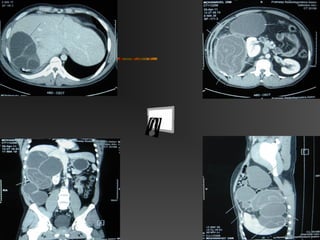

Case – 2 (Hydatid – Abdomen )

 29 yrs

 Pain Abd / Swelling – 6 mths

 UW – CA – 3 yrs Back

 P/A – Liver + / + masses abd

 CBC – WNL

 CT Scan – Hydatid Cyst

Multiple Liver & Mes.